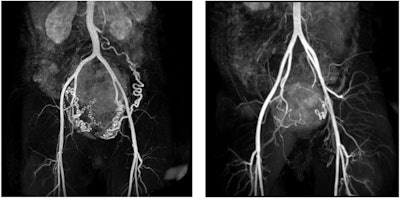

MR angiography images of subserosal/intramural uterine fibroid with a diameter of 144 mm in the dorsal uterine wall and hypertrophic arteria overica in a 41-year-old woman (left), and subserosal pedunculated fibroid of a 42-year-old woman with a 69 mm diameter (right).